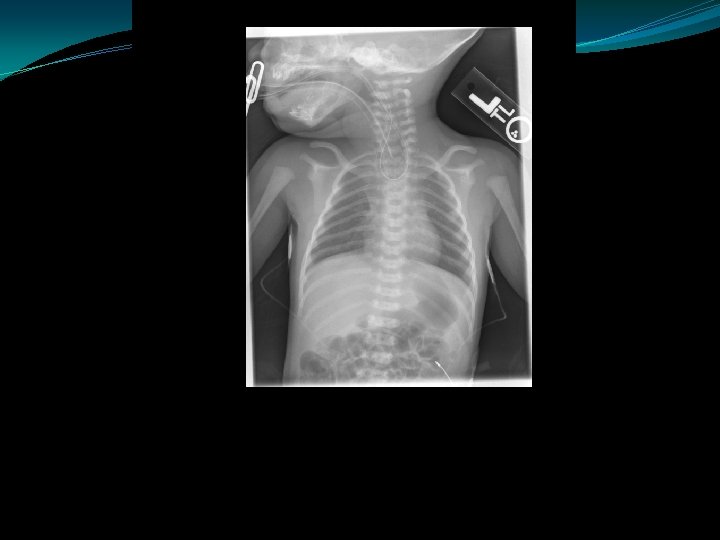

TEF/EA

Tracheo-esophageal fistula and esophageal atresia

Esophageal Atresia & Tracheo-esophageal Fistula Symptoms �Respiratory distress from aspiration �Poor handling of secretions: drooling, frequent suctioning, choking or other symptoms with feeding �Inability to pass OG/NG to stomach �Abdominal distention may occur with swallowing of air through TEF or due to associated anal atresia

Esophageal Atresia & Tracheoesophageal Fistula Associated Problems �Prematurity �RDS, pulmonary aspiration �VACTERL (vertebral anomalies, anal atresia, cardiac anomalies, TEF, renal, limb) �Abdominal distention due to air passed through TEF can cause gastric perforation

Esophageal Atresia & Tracheoesophageal Fistula: Management �CXR with tube to the pharyngeal pouch �LIS to the pharyngeal tube �Blood culture, ampicillin and gentamicin �Manage respiratory problems �Examine for anomalies: VACTERL